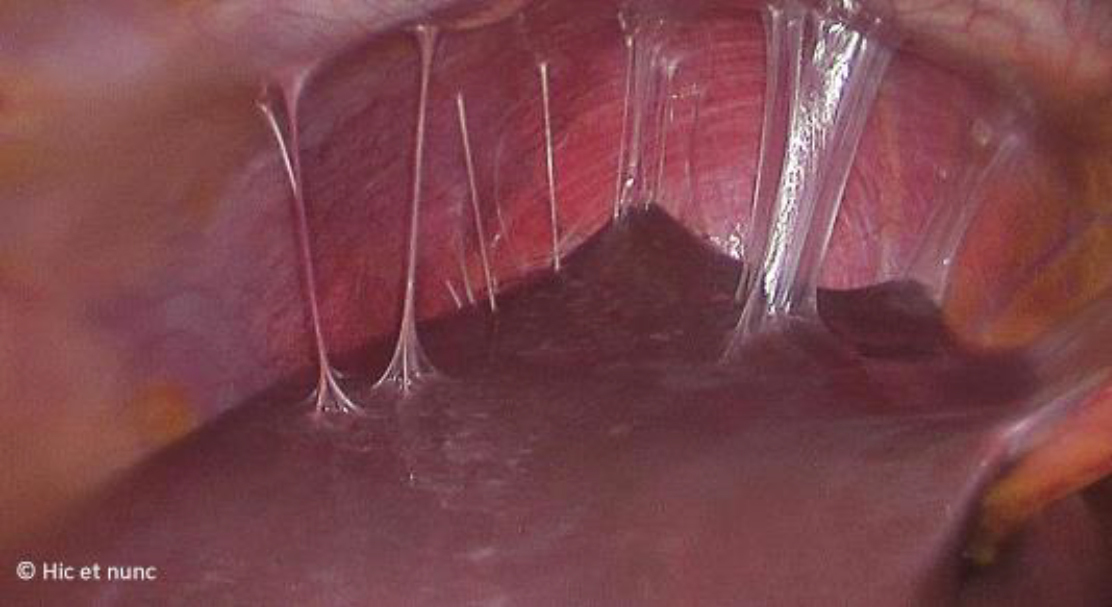

Vous décidez de réaliser en urgence une cœlioscopie exploratrice qui objective un saignement modéré au niveau du kyste de l’ovaire que vous parvenez difficilement à arrêter. En explorant la cavité abdominale vous objectivez ceci (fig. 7) :

Figure 7

Les adhérences « en cordes de violon » entre le foie et le péritoine sont typiques d’une périhépatite secondaire à une infection active ou à un antécédent d’infection à Chlamydia. Il s’agit d’un syndrome de Fitz-Hugh-Curtis.

Les infections génitales hautes peuvent entraîner des adhérences et la destruction des cils tubaires qui augmentent le risque d’infertilité et de grossesse extra-utérine.